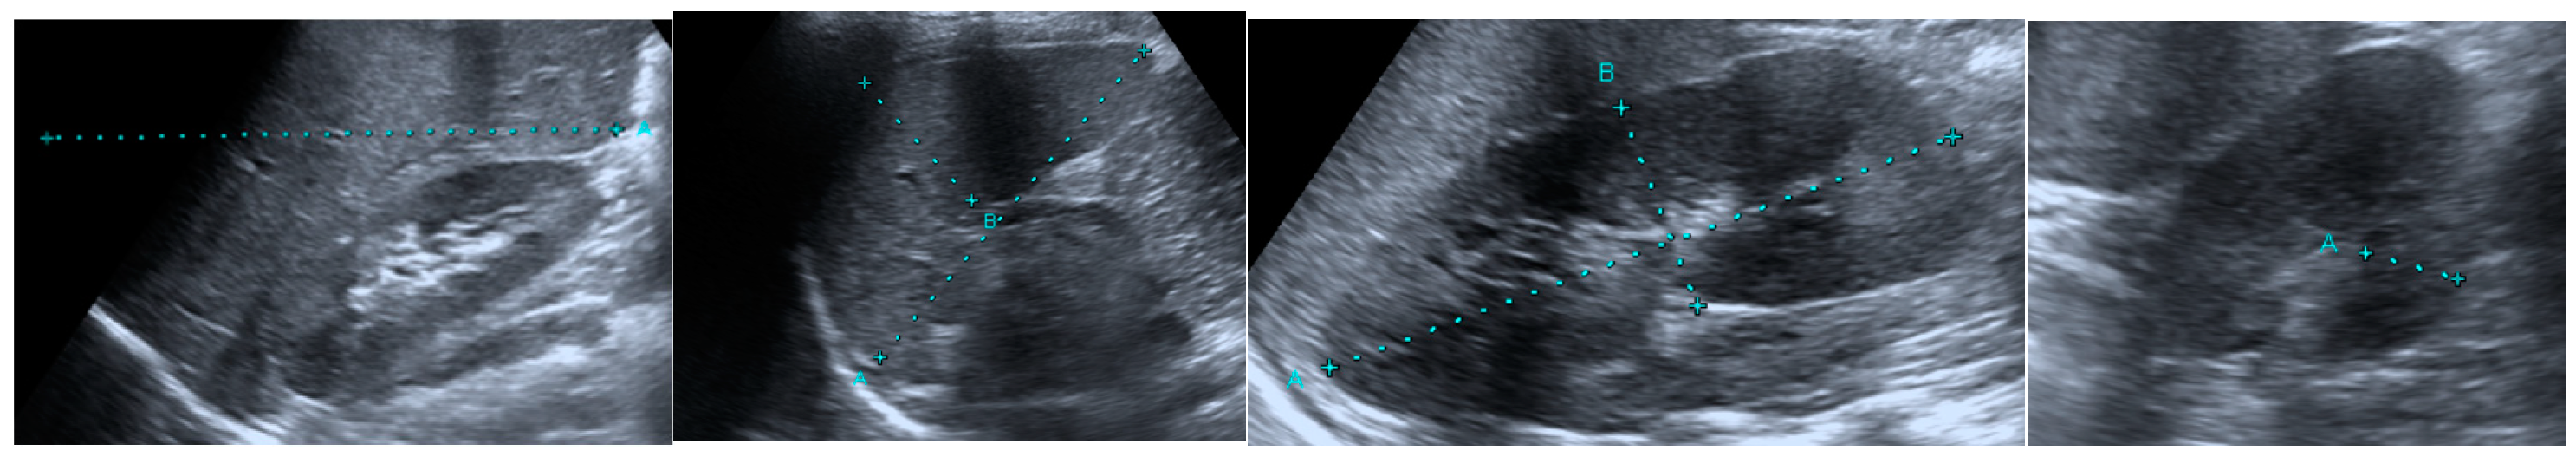

2.2. Ultrasonographic Evaluation